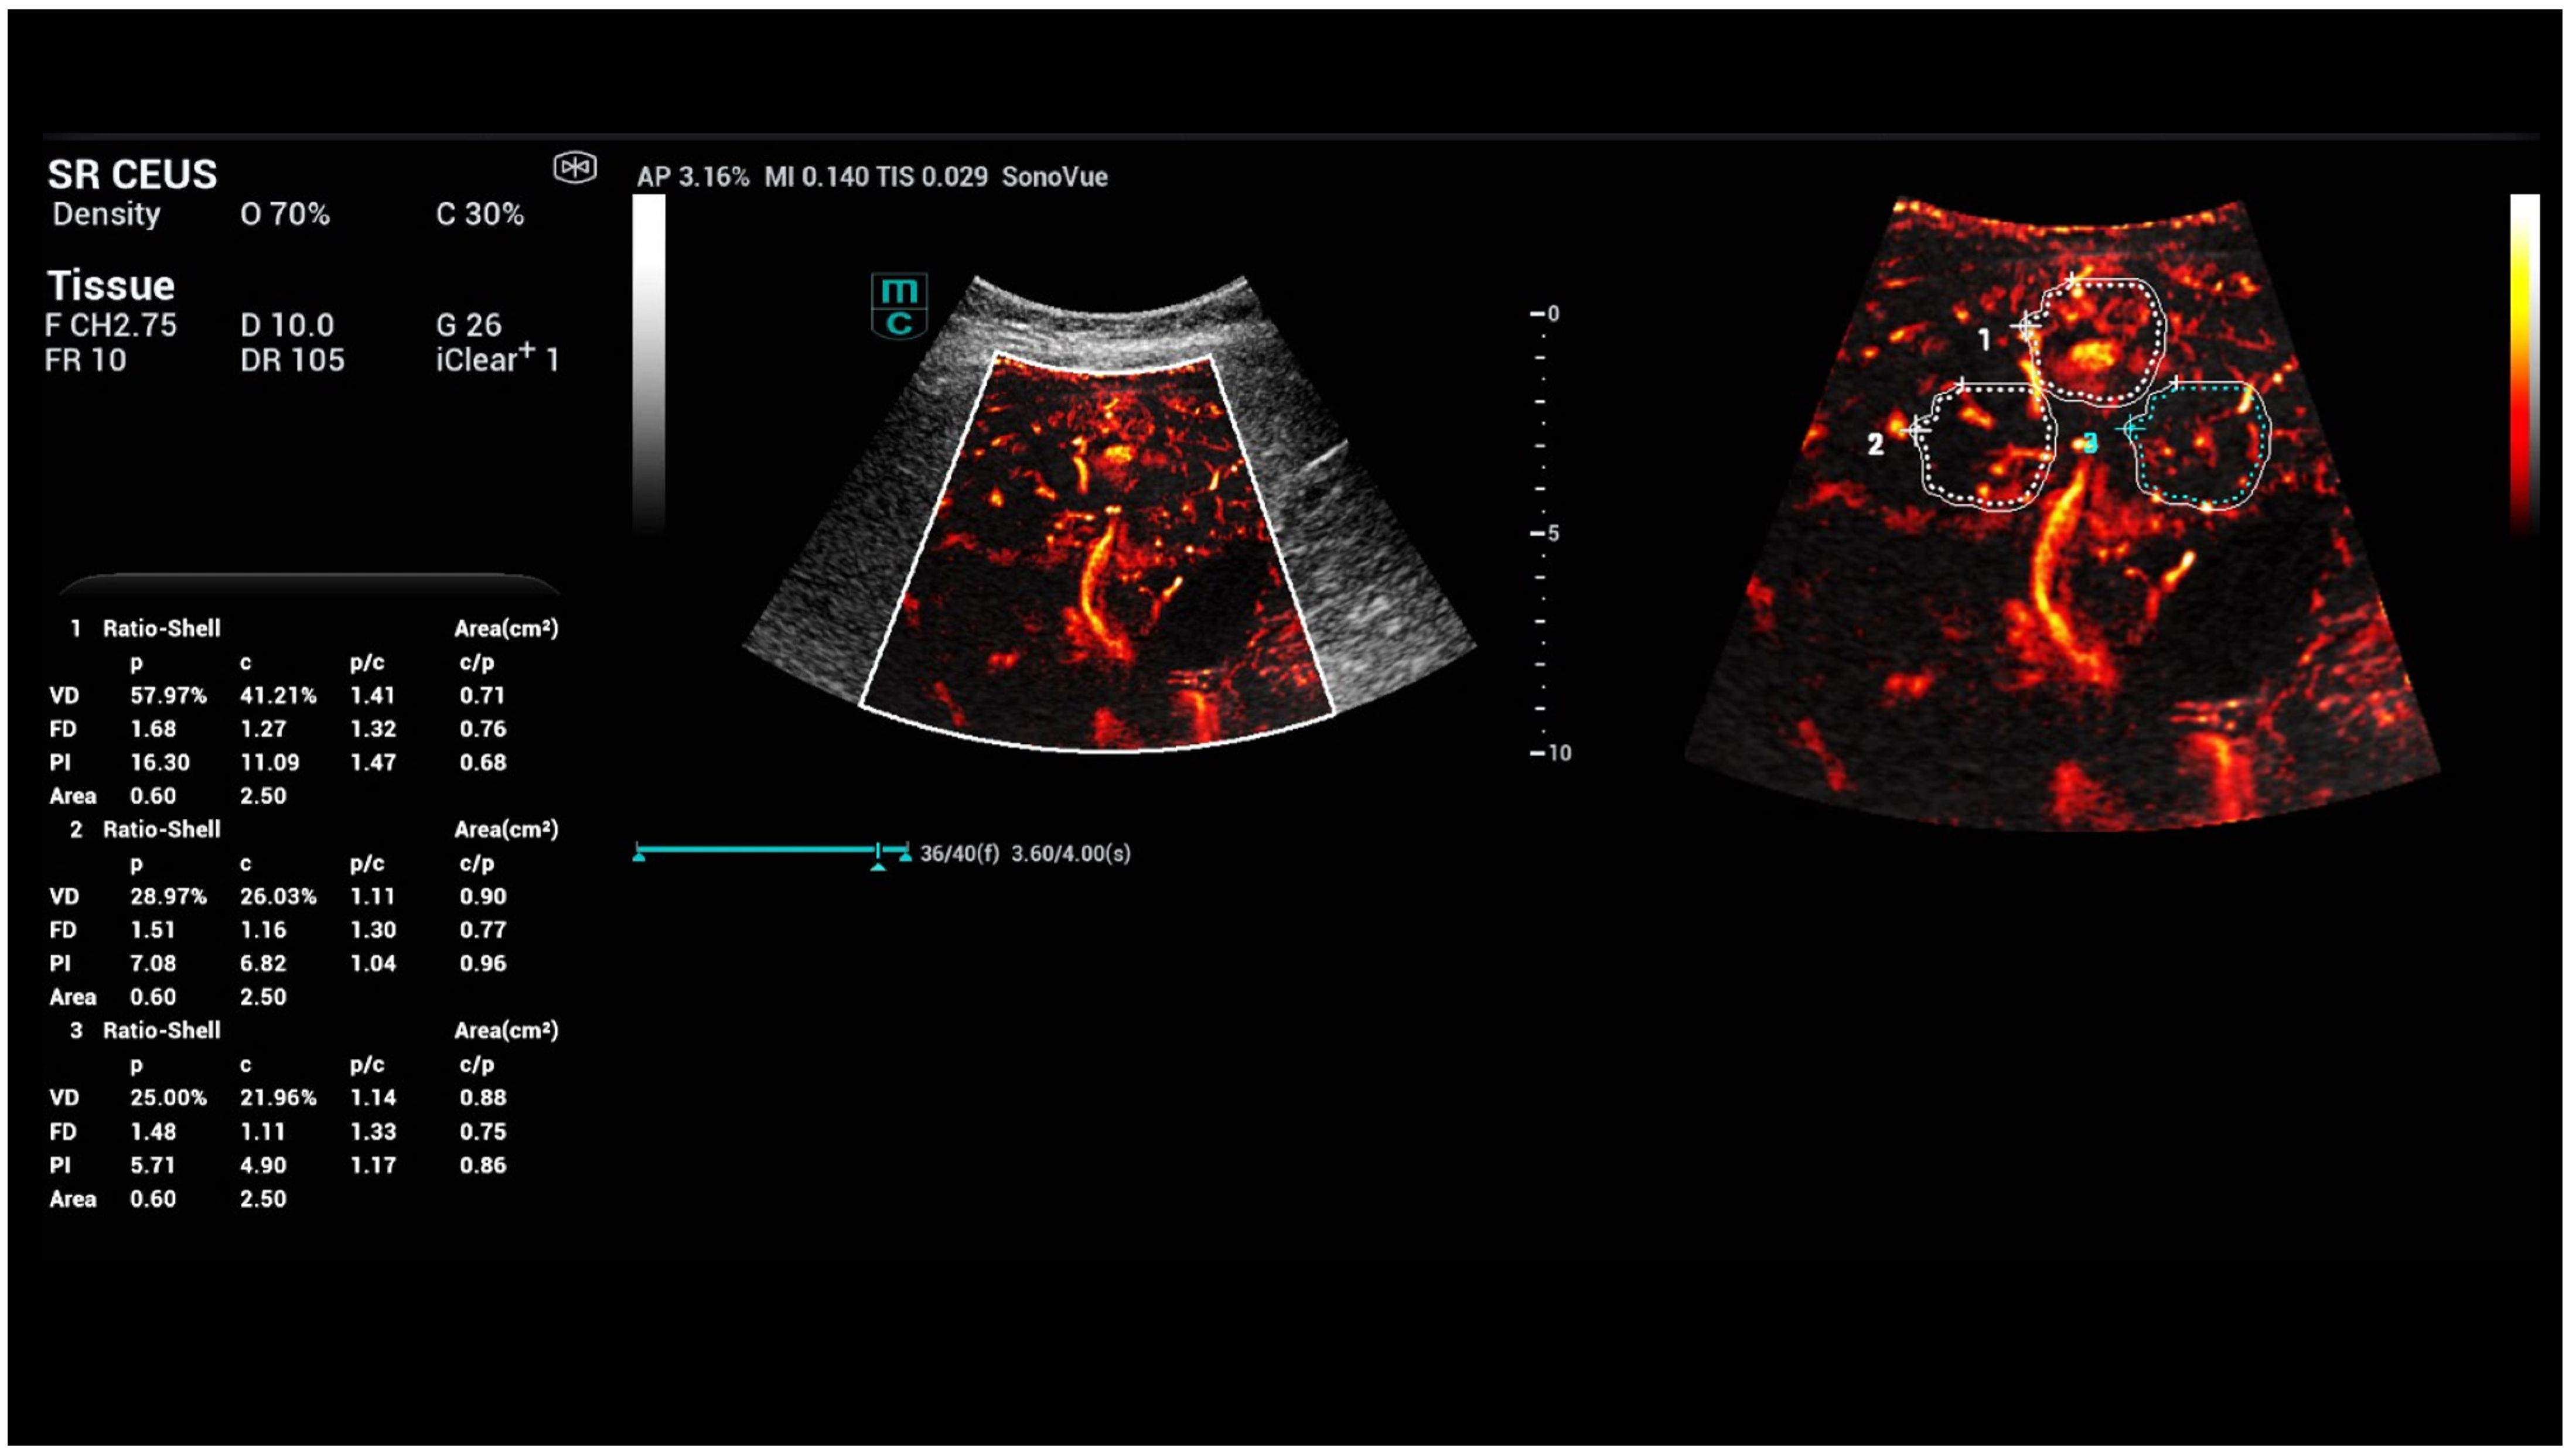

- Kaiser, U.; Vehling-Kaiser, U.; Kück, F.; Gilanschah, M.; Jung, F.; Jung, E.M. Super-Resolution contrast-enhanced ultrasound examination down to the microvasculature enables quantitative analysis of liver lesions: First Results. Life 2025, 15, 991. [Google Scholar] [CrossRef]

- Schelker, R.C.; Andorfer, K.; Putz, F.; Herr, W.; Jung, E.M. Identification of two distinct hereditary hemorrhagic telangiectasia patient subsets with different hepatic perfusion properties by combination of contrast-enhanced ultrasound (CEUS) with perfusion imaging quantification. PLoS ONE 2019, 14, e0215178. [Google Scholar] [CrossRef]